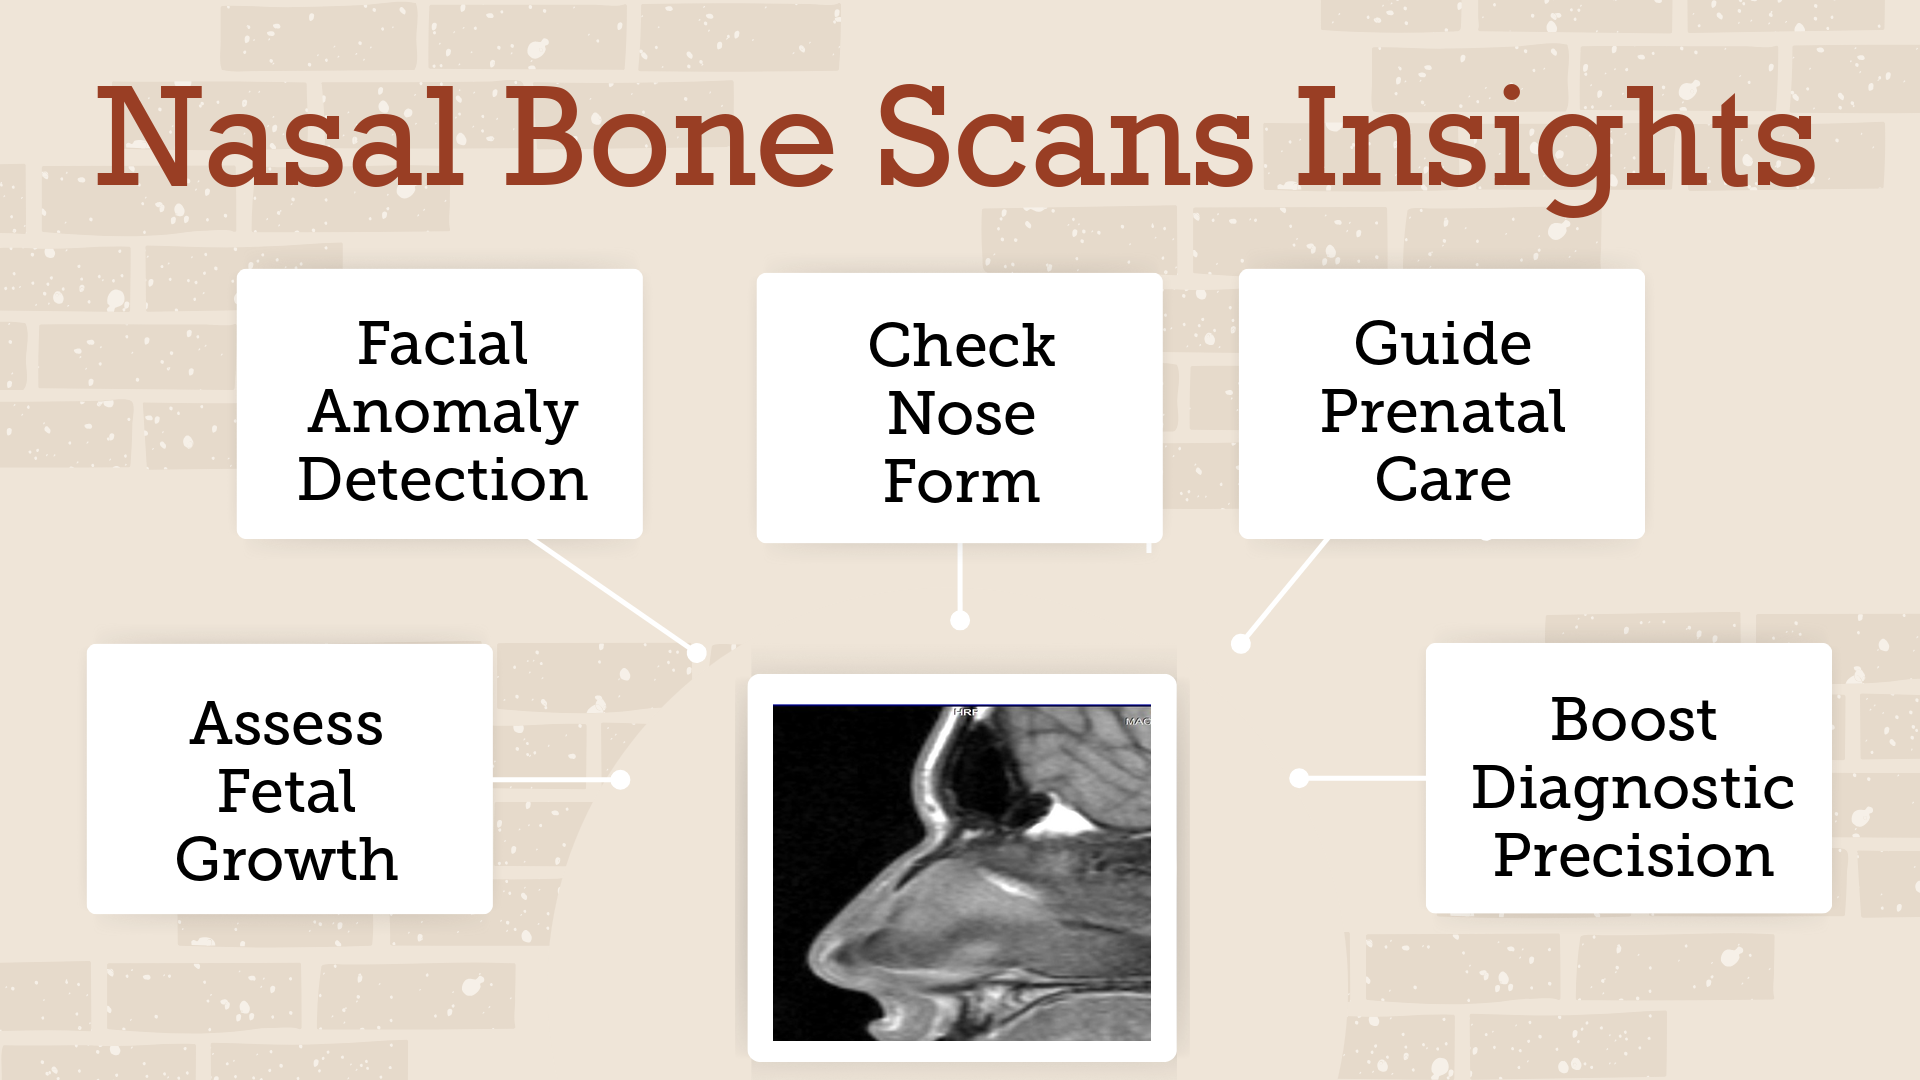

Everything You Need to Know About Nasal Bone Scans: A Comprehensive Guide!

Understanding the Nasal Bone Scan A nasal bone scan is a medical imaging test. Doctors use it to examine the bones of the nose. By